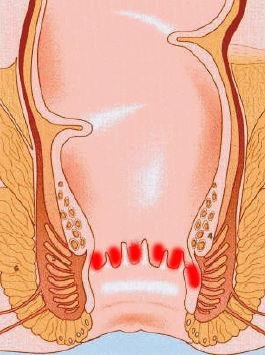

ANAL KRİPTİT (PAPİLLİT)

• Anal kriptit və ya kriptoqlandulit anal kanalda dişli xətt səviyyəsindəki kripatların və bura açılan vəzilərin iltihablaşmasıdır, paraproktitlərə səbəb ola bilir (Şəkil 1).

duz img 27

Şəkil 1. Anal kriptit.